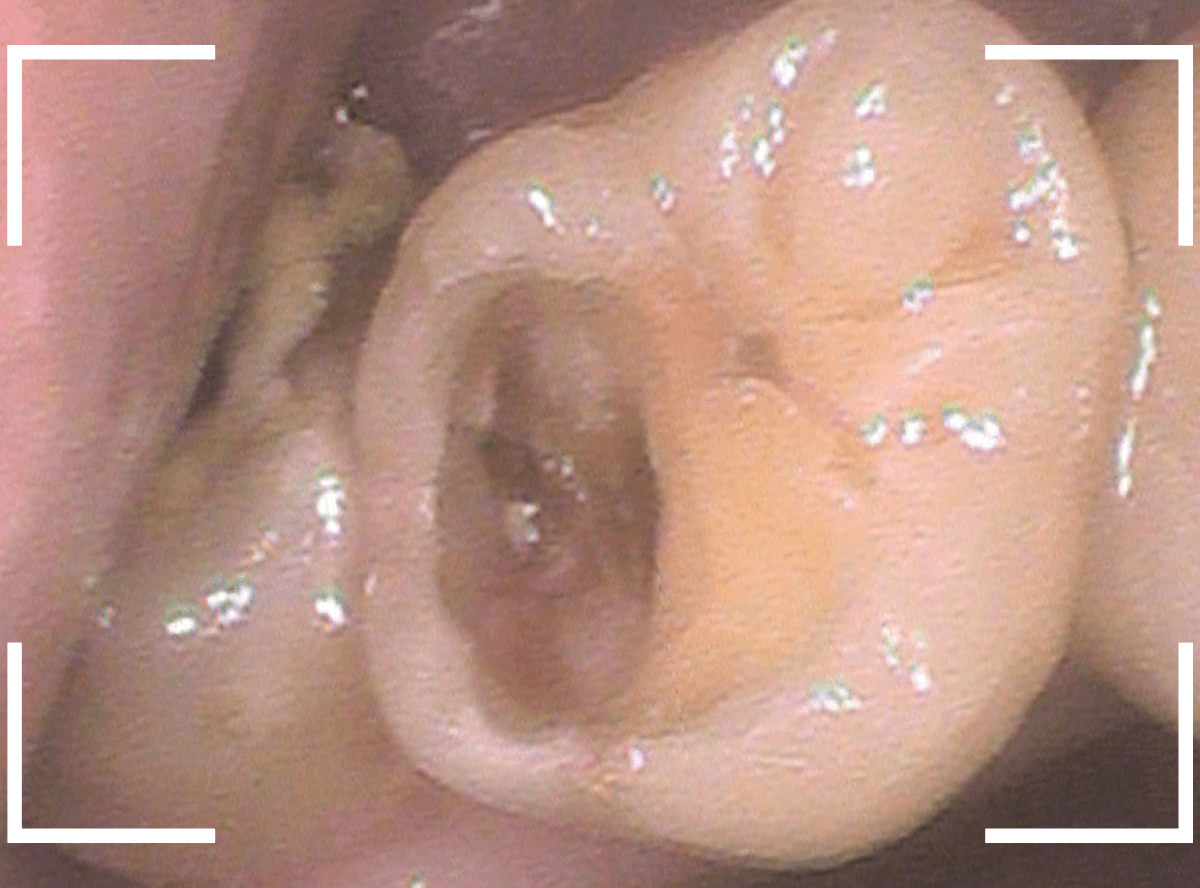

ここでは、比較的簡単なおやしらずの抜歯の例を中心にご紹介します。

このようなおやしらず、あなたはありませんか?